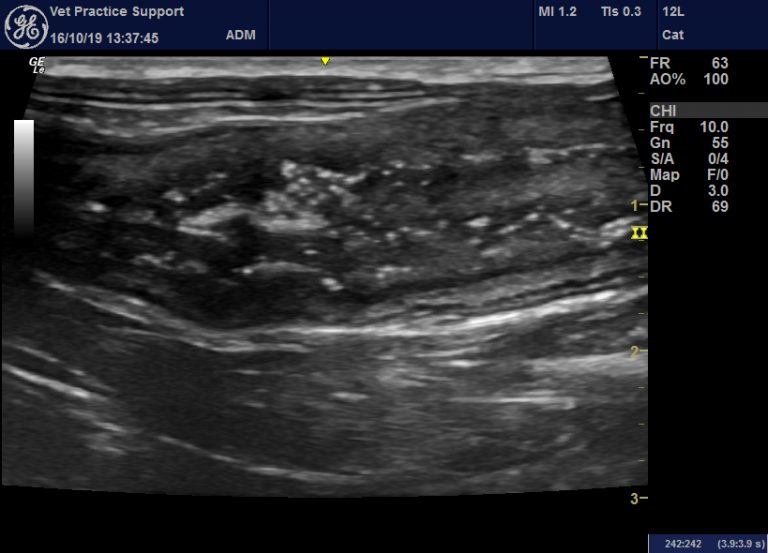

From www.vetpracticesupport.com

An acute enterocolitis in cats with striking sonographic features is What Causes Thickening Of The Intestinal Wall In Cats Feline inflammatory bowel disease (ibd) is a condition in which a cat’s gastrointestinal (gi) tract becomes chronically irritated and inflamed. One study found that 99% of cats that had chronic gi signs and thickened small intestinal walls on ultrasound examination had underlying pathology. If the object is long enough to trail into the intestines, normal intestinal movement tends to cause. What Causes Thickening Of The Intestinal Wall In Cats.

Abdominal ultrasound images of a 5yearold cat (case 1) with an What Causes Thickening Of The Intestinal Wall In Cats Inflammatory bowel disease (ibd) occurs when an (often unknown) trigger causes white blood cells to infiltrate into the walls of any part of the. Inflammatory cells infiltrate the walls of the gi tract, thickening. Feline inflammatory bowel disease (ibd) is a condition in which a cat’s gastrointestinal (gi) tract becomes chronically irritated and inflamed. If thickening is found, there are. What Causes Thickening Of The Intestinal Wall In Cats.